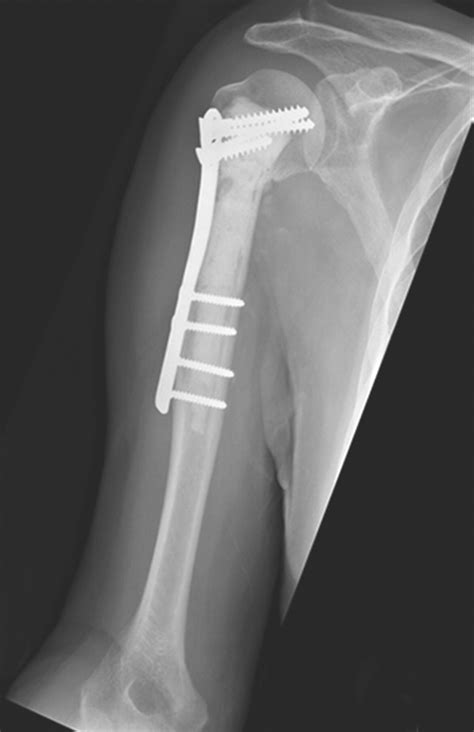

• Surgical Treatment:

• Open Reduction and Internal Fixation (ORIF): Surgery to realign the bone fragments and secure them with plates, screws, or rods.

• Shoulder Replacement: In severe cases, especially in older adults, a partial or total shoulder replacement may be necessary.